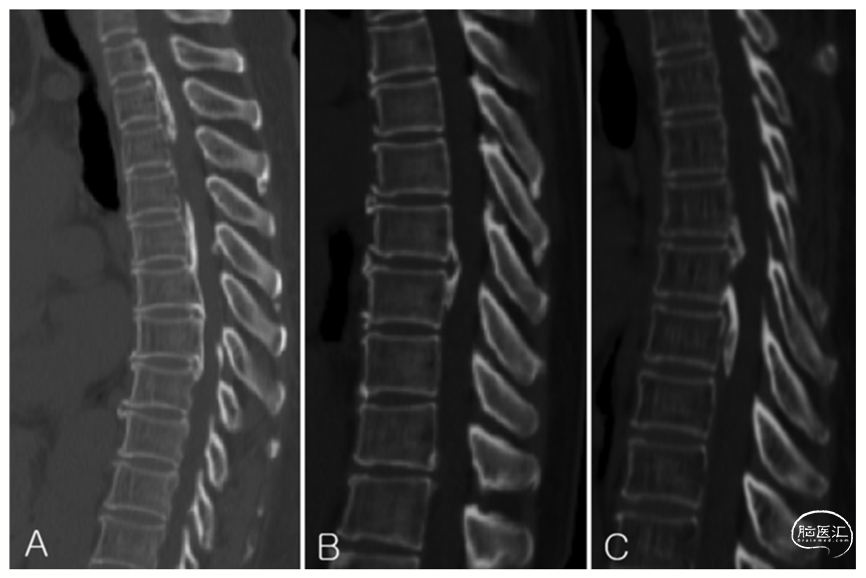

注:胸椎后纵韧带骨化